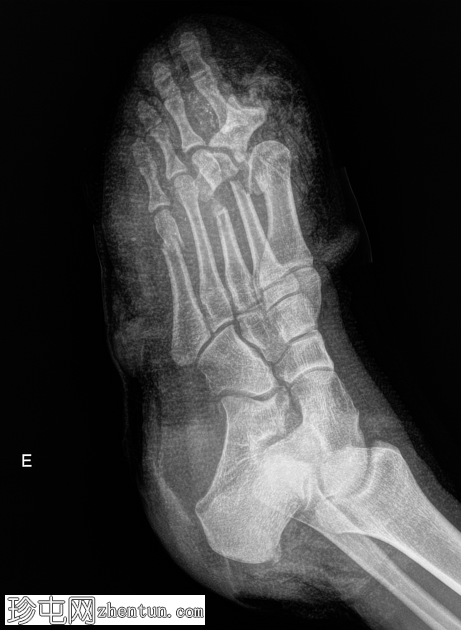

X线片

正位

术后即刻影像

经Lisfranc跗跖关节截肢(Lisfranc截肢术)。

骨突处软组织覆盖良好。

考虑到软组织损伤的严重程度以及伤口愈合的担忧,选择Lisfranc截肢而非经跖骨截肢。